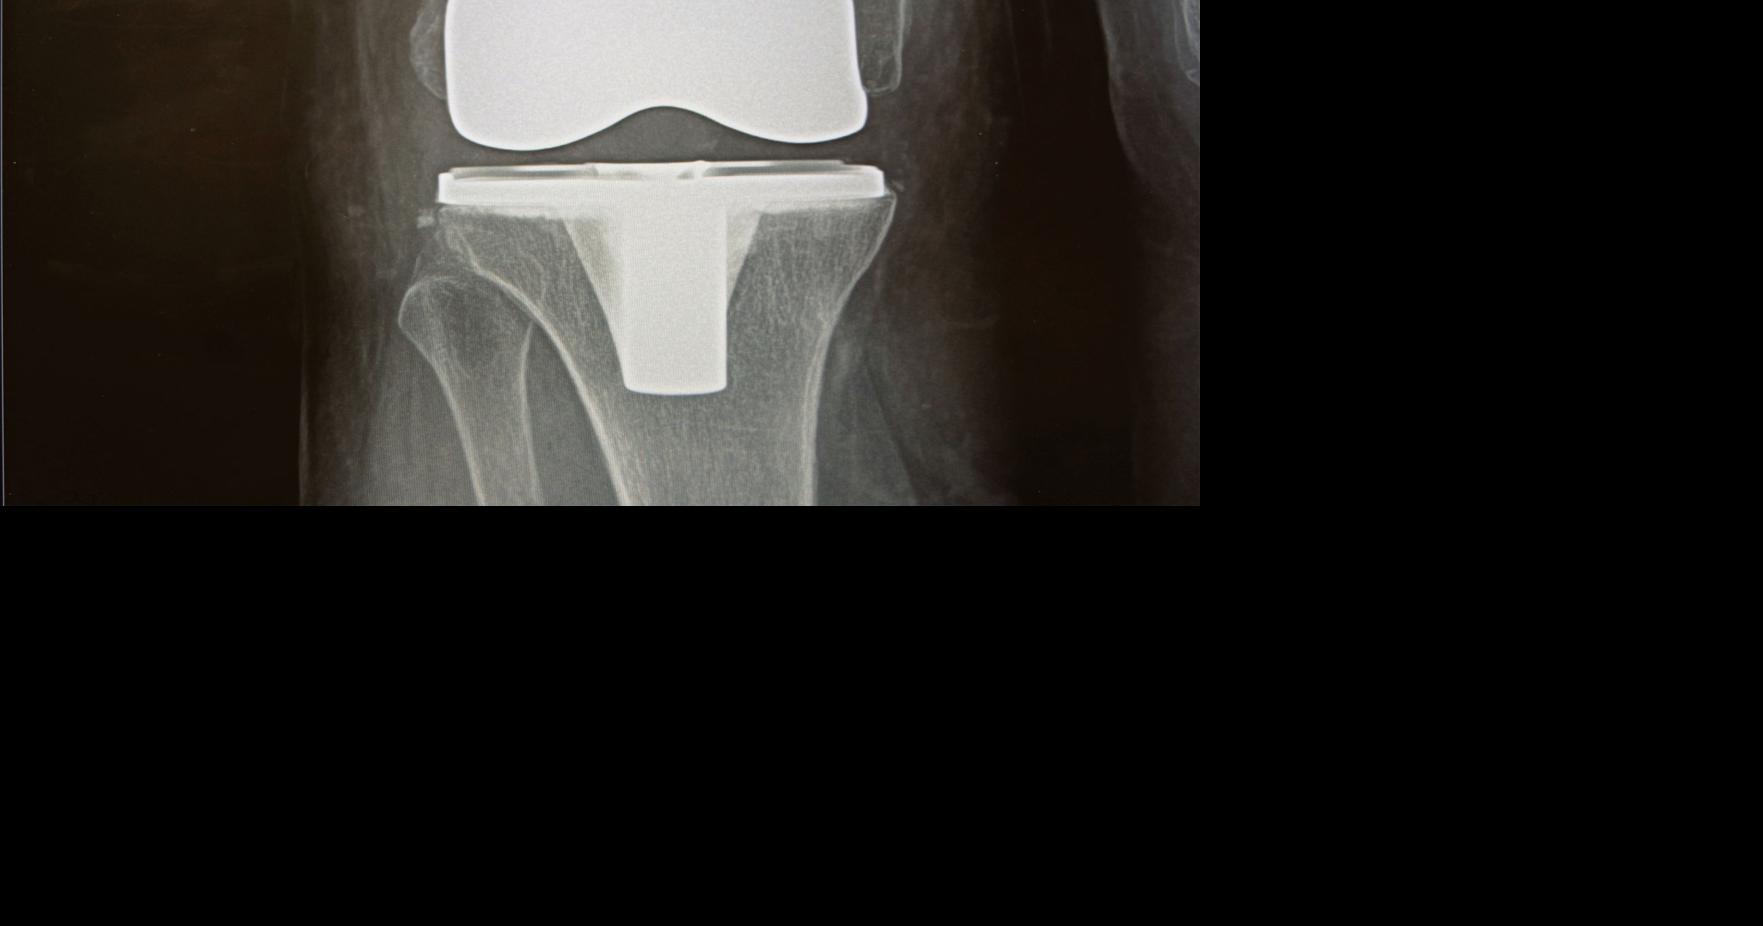

When good joints go bad Orthopedic joint replacement surgeries on the rise Can Joints Go Bad Learn about the types, diagnosis,. Although osteoarthritis can damage any joint, the disorder most commonly affects joints in your hands, knees, hips and spine. Learn about the 10 common symptoms of oa, how it differs from rheumatoid arthritis, and how it's treated. Chronic knee pain can mean you’re most likely to experience joint problems with the opposite leg, your hips,. Can Joints Go Bad.